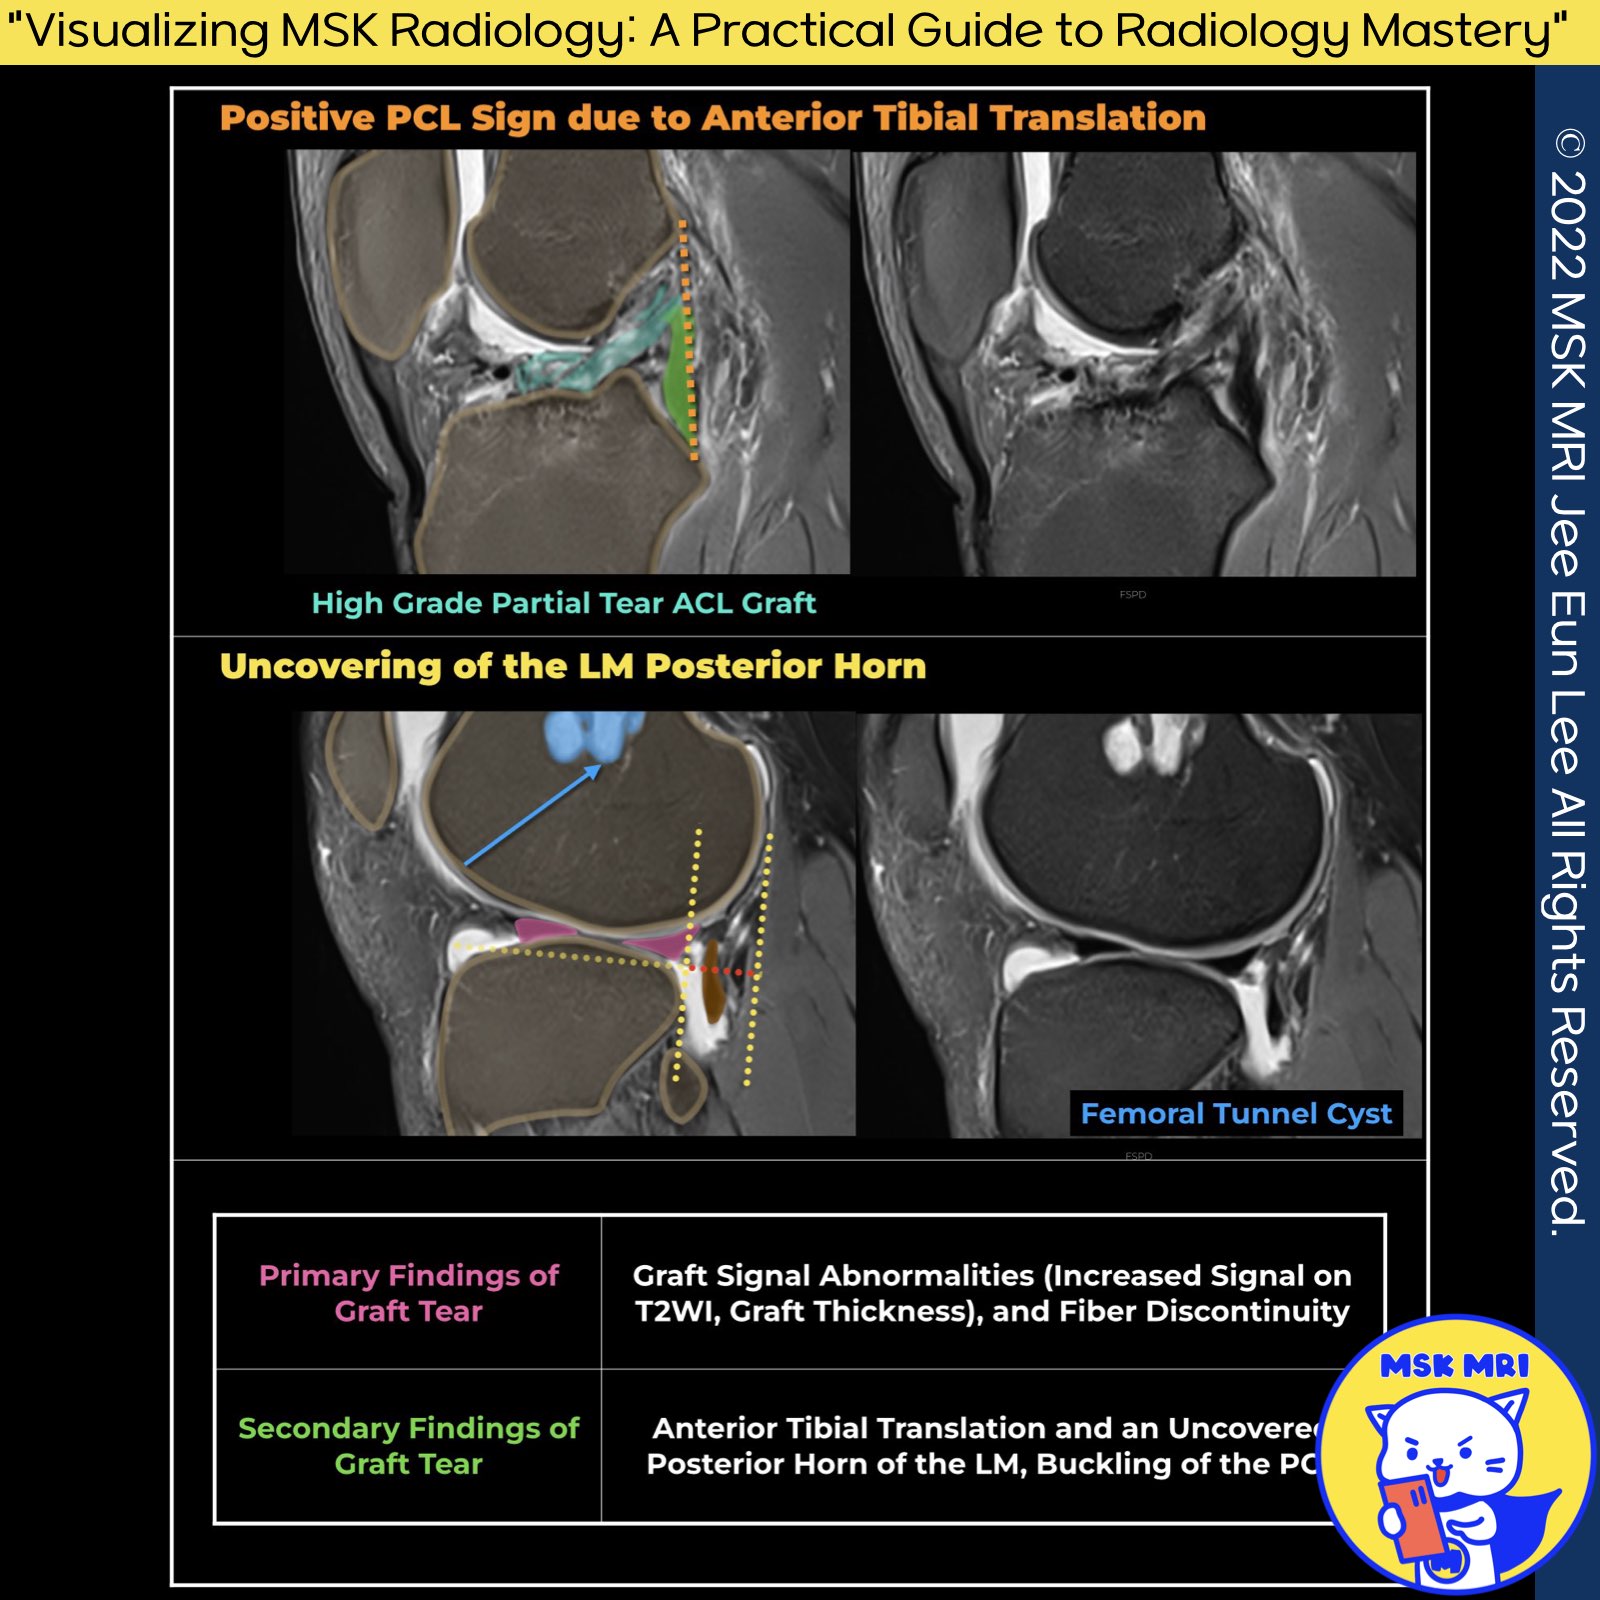

✅ Differentiating Revascularization from Graft Tear

- Secondary indicators of graft rupture include uncovering the lateral meniscus's posterior horn, visualization of the complete lateral collateral ligament in one coronal slice, buckling of PCL, and anterior translation of the tibia.

- The observation of secondary signs is crucial in distinguishing between graft tears and the normal revascularization process of the graft, which might present a similar appearance on imaging.